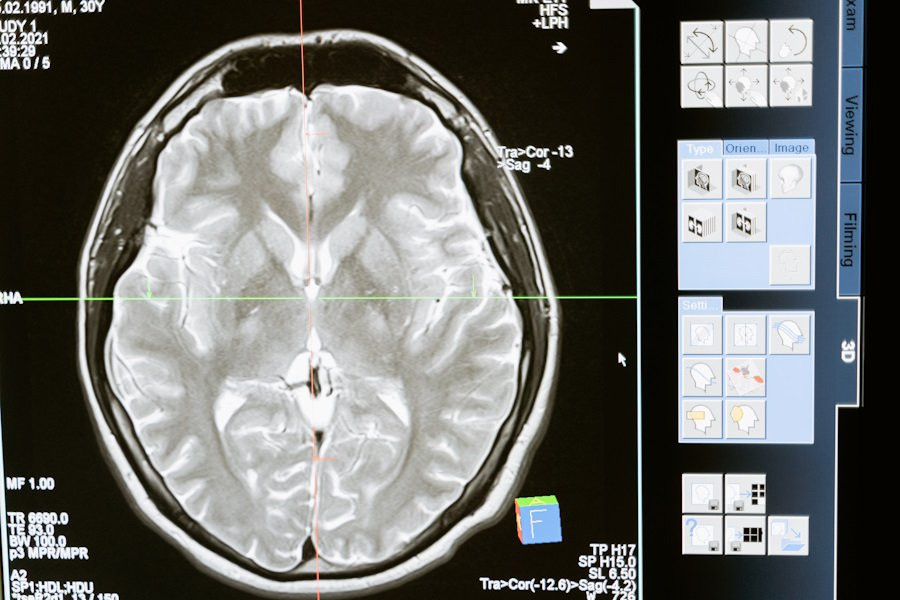

Ранее ученые использовали функциональную магнитно-резонансную томографию (фМРТ), чтобы определить области мозга, связанные с языковой обработкой. Однако фМРТ, которая измеряет изменения кровотока, не обладает достаточной разрешающей способностью для выявления работы небольших популяций нейронов. Это ограничивало возможность точно определить, какие функции выполняют отдельные группы нейронов.